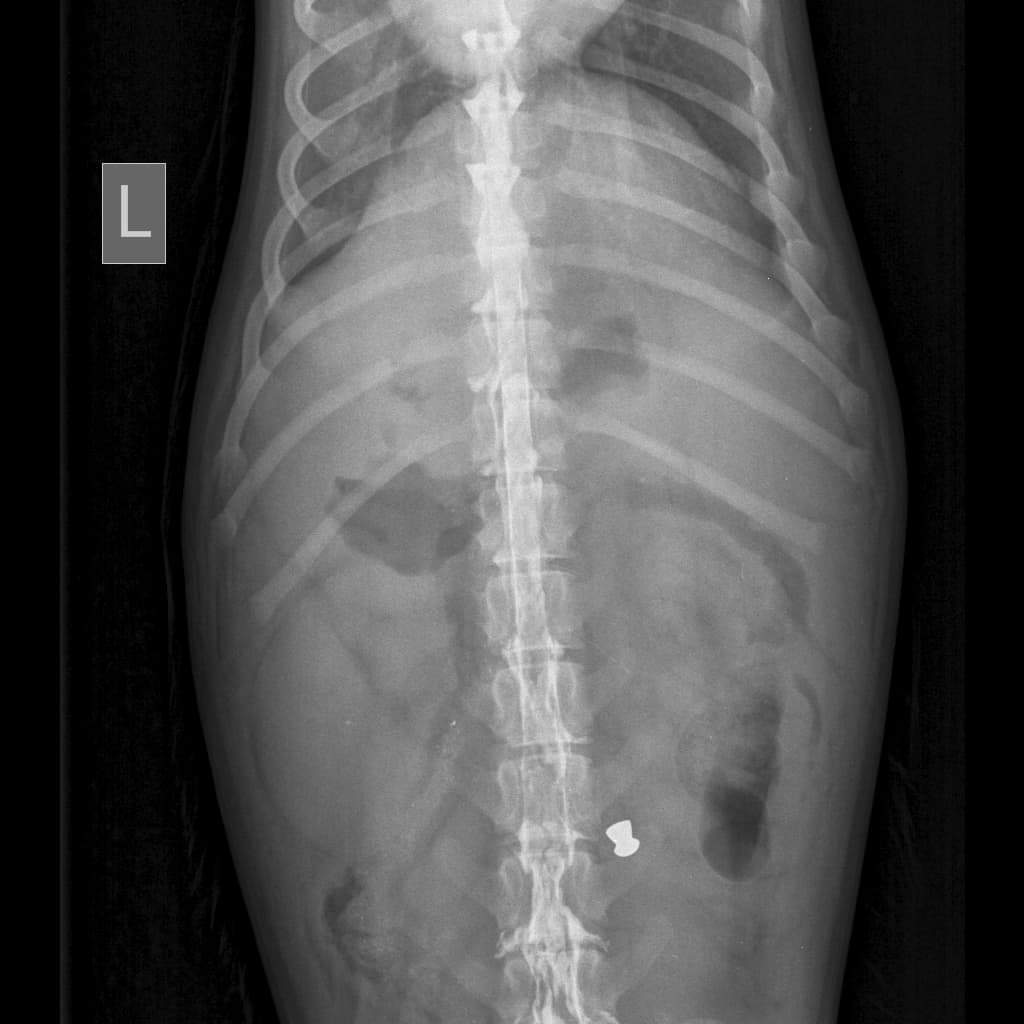

Merkel is about 3 years old. When he was a small puppy, he was shot. The bullet landed very close to his spine, and he lost the use of his back legs. As he grew, his legs became hyper extended and could no longer bend.

They stuck out to the side and were causing him mobility issues. Plus because they were hyper extended, they became a great risk of getting fractured.

Because of his hyperextension, we decided along with orthopedic specialists, that removing his legs would be his best option.

Merkel is now a double amputee. He did so well through his surgery and recovery. He now has a hind end cart so he can go for walks.